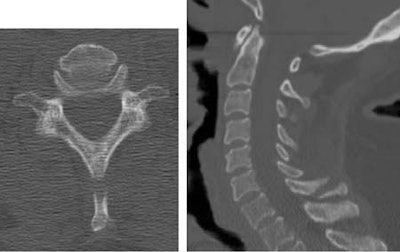

MDCT images are acquired over 25 seconds using 2.5-mm slice thickness, 2.5-mm image spacing, HQ mode. MDCT images are reconstructed to 1.25-mm slice thickness, 1-mm image spacing. Sagittal and coronal reformations are created using 2.5-mm slices and 2.5-mm spacing.

![]() |